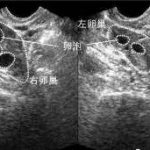

试管婴儿对精子的要求主要体现在形态、浓度、活力这几个方面。精子形态首先要保证正常,正常的精子形态宛如蝌蚪,头部偏扁,呈卵圆形。精子浓度:最好的精子浓度为2000/ml,精子浓度过低的话,存活率也就较低,会影响受精。精子活力:正常情况下,排精一个小时内,有活力的精子要达到70%以上,通常情况下,做供卵试管,精子活力要到达60%。